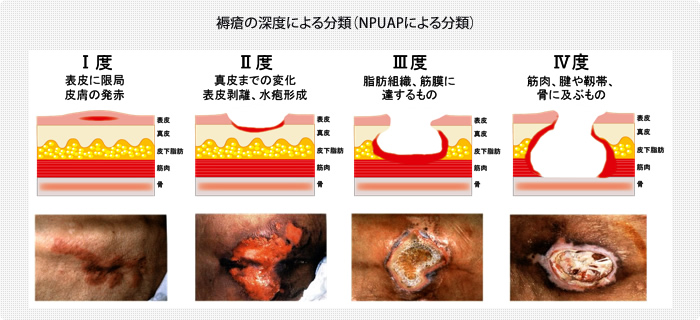

褥瘡の重症度分類を理解しようステージ分類NPUAP、EPUAP分類。

急性期の褥瘡と慢性期の褥瘡とは浅い褥瘡、深い褥瘡進展過程。

褥瘡治療① 実はあまり知られていない必須の褥瘡知識:褥瘡の治療法は深さによって異なる! -皮膚科専門医が伝授!医療従事者のための高齢者皮膚トラブル対策講座。

褥瘡治療① 実はあまり知られていない必須の褥瘡知識:褥瘡の治療法は深さによって異なる! -皮膚科専門医が伝授!医療従事者のための高齢者皮膚トラブル対策講座。

急性期の褥瘡と慢性期の褥瘡とは浅い褥瘡、深い褥瘡進展過程。

褥瘡治療① 実はあまり知られていない必須の褥瘡知識:褥瘡の治療法は深さによって異なる! -皮膚科専門医が伝授!医療従事者のための高齢者皮膚トラブル対策講座。

医師監修・作成 褥瘡 床ずれ の検査や分類などMEDLEY メドレー。

褥瘡治療① 実はあまり知られていない必須の褥瘡知識:褥瘡の治療法は深さによって異なる! -皮膚科専門医が伝授!医療従事者のための高齢者皮膚トラブル対策講座。